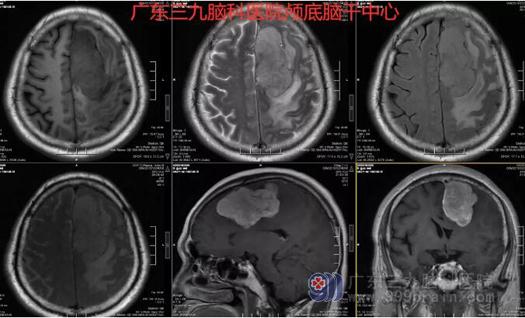

图2:术前MR示左侧额部镰旁示一团块状占位性病变,大小约72mm×48mm×39mm,边界清,呈长T1长T2、FLAIR序列高信号影,其内信号欠均,示斑片状稍短T2信号影,增强后病变呈明显欠均匀强化,邻近大脑镰示线样强化;病变周缘示线样脑脊液样信号影,周围脑组织受压推移并示片状水肿信号影,相应脑沟变浅,邻近左侧侧脑室受压变窄,中线结构略向右偏。右侧放射冠区示斑片状长T1长T2、FLAIR序列内低外高信号影,双侧基底节区示斑片状等T1长T2、FLAIR序列高信号影,双侧大脑半球白质内示多发斑点状、斑片状等T1长T2、FLAIR序列高信号影,增强后未见异常强化。